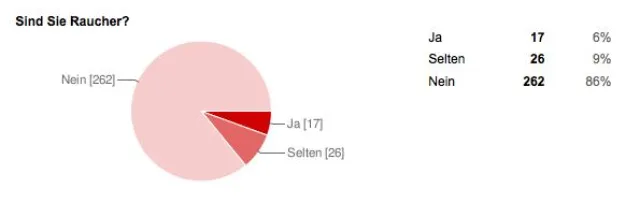

Rauchen ist nicht nur schädlich

Einer Umfrage zufolge leiden 15 mal mehr Nichtraucher unter Aphthen als Raucher.

In einer Onlineumfrage unter 303 Betroffenen gaben 87,5% an Nichtraucher zu sein. 5,5% waren Raucher, weitere 7,0% bezeichneten sich als Gelegenheitsraucher.